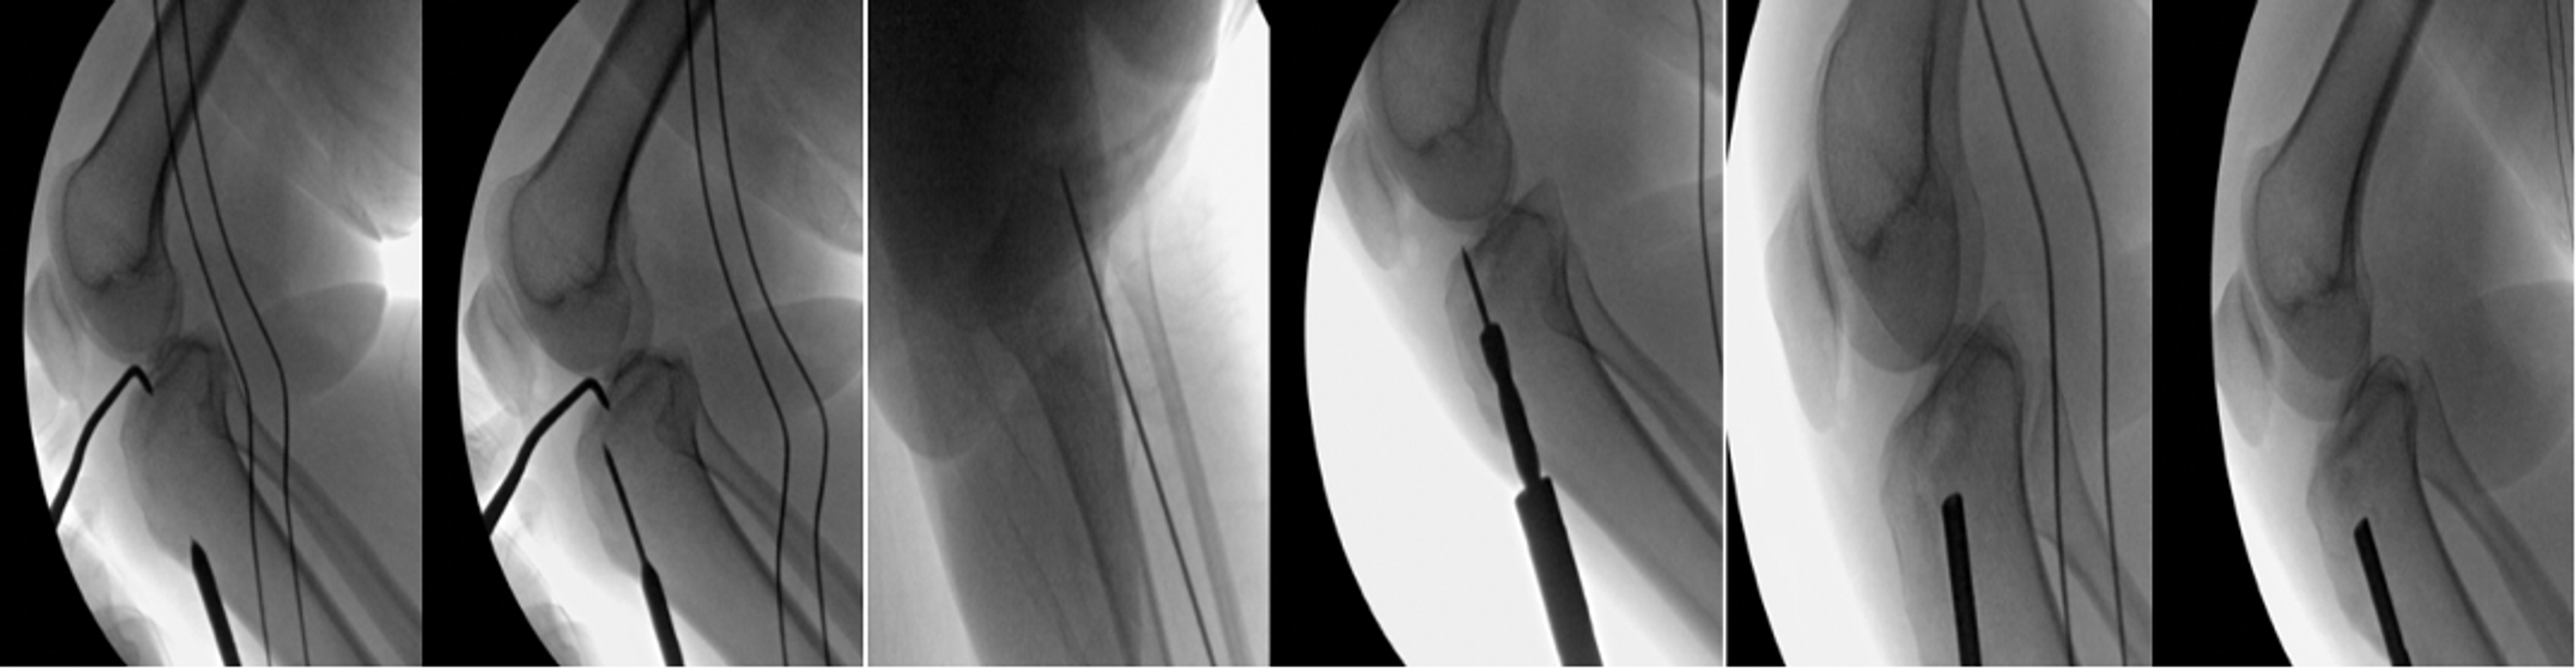

Following a careful evaluation of the pre-operative CT scan, we planned to achieve a combined intraoperative arthroscopic- and fluoroscopic-guided reduction of the articular depression through a lateral cortical window. The fracture was fixed using a minimally invasive fixation technique. The patient was supine on a Jackson table under general anesthesia. She received 2 g of intravenous cefazolin for infection prophylaxis. Non-sterile tourniquet was applied. The right knee was prepared, draped, and flexed to 90 degrees using foot support and a lateral thigh kidney shape support. A standard lateral and medial anterior arthroscopic portals were made. Diagnostic knee arthroscopy was conducted and the fracture was assessed. No other knee pathologies were identified. The inflow pressure was kept to a minimum throughout the case to decrease the risk of fluid extravasation and reduce the subsequent potential for increased compartment pressure. An anterior cruciate ligament (ACL) guide was used to place a drill-tipped guide pin in the center of the depressed fragment through a small incision in the proximal anterolateral aspect of the tibia (Figure 2).

Intraoperative anterior-posterior (AP) and lateral fluoroscopy were used to confirm that the guidewire was drilled into the desired fragment with the appropriate trajectory depending on the direction chosen on pre-operative CT. A size 8 coring reamer was used to circumferentially open the tibial cortex while as little bone as possible was removed. A bone impactor was used to elevate the depressed fragment. The anatomical reduction was obtained and confirmed by arthroscopy and fluoroscopy (Figure 3).